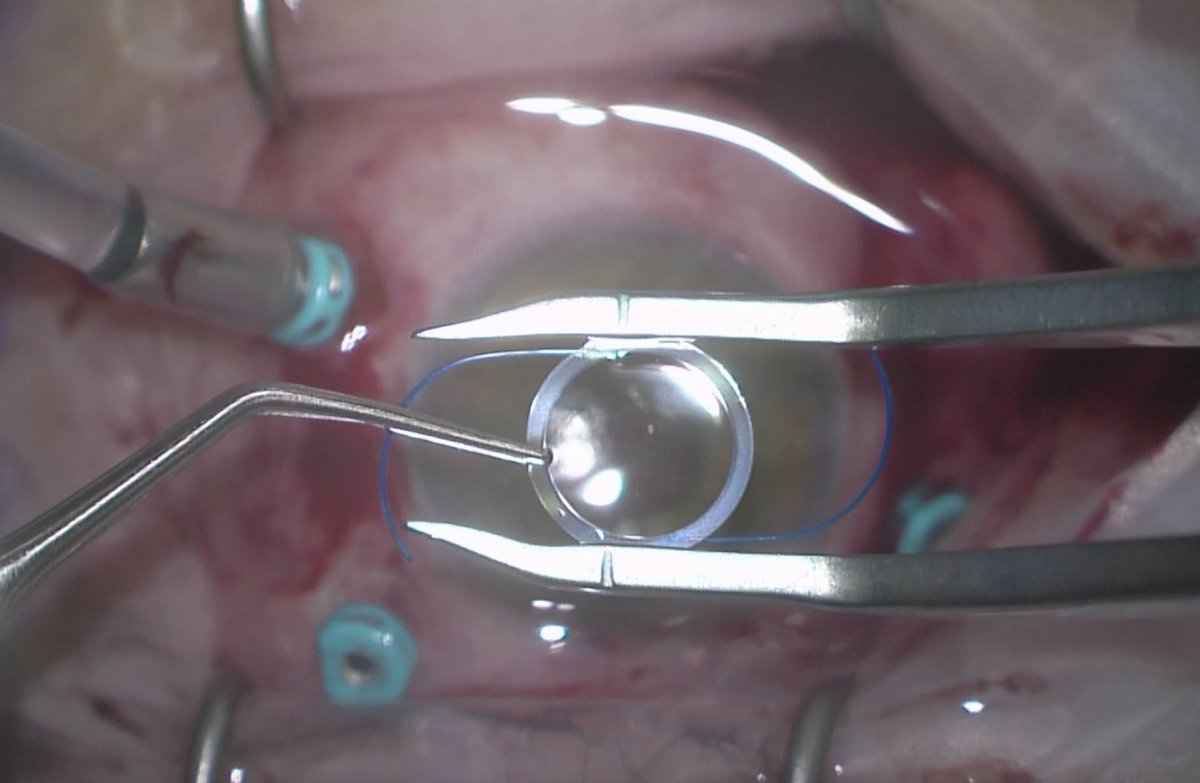

Incredible teachers and amazing co-residents is what makes residency great. This week Dr. Zhang (future retina surgeon) performed a vitrectomy and brought an IOL to the AC. I finished the explant and did the Yemane scleral fixation. #teamwork #ophthalmology #ophthotwitter